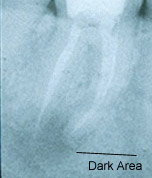

Answer:A root canal is a root filling. It is necessary when the nerve in a tooth is injured and/or dies. A dead nerve sometimes can be seen on an x-ray. This is noted by the dark area at the bottom of the root tips on the first radiograph (x-ray) below. Root canal therapy can be done in one or several visits. A root canal helps an infected tooth heal. During the procedure the inside of the tooth is cleaned and filled. Afterwards, the tooth will need either a filling or a post & core and crown.

The radiograph (x-ray) series below shows an example of the root canal process. This patient initially presented with infection and pain but had immediate relief of symptoms following the first visit. Complete healing is noted on the one-year root canal followup radiograph (x-ray). The healing is evidenced by an absence of a dark area around the root tips, indicating that new bone has grown in the area of previous infection. The very white area inside the roots is the root canal filling material which is gutta percha, a derivative of a South American gum tree. This material is commercially packaged as root canal filling material and is recommended by the University of Connecticut Dental School.